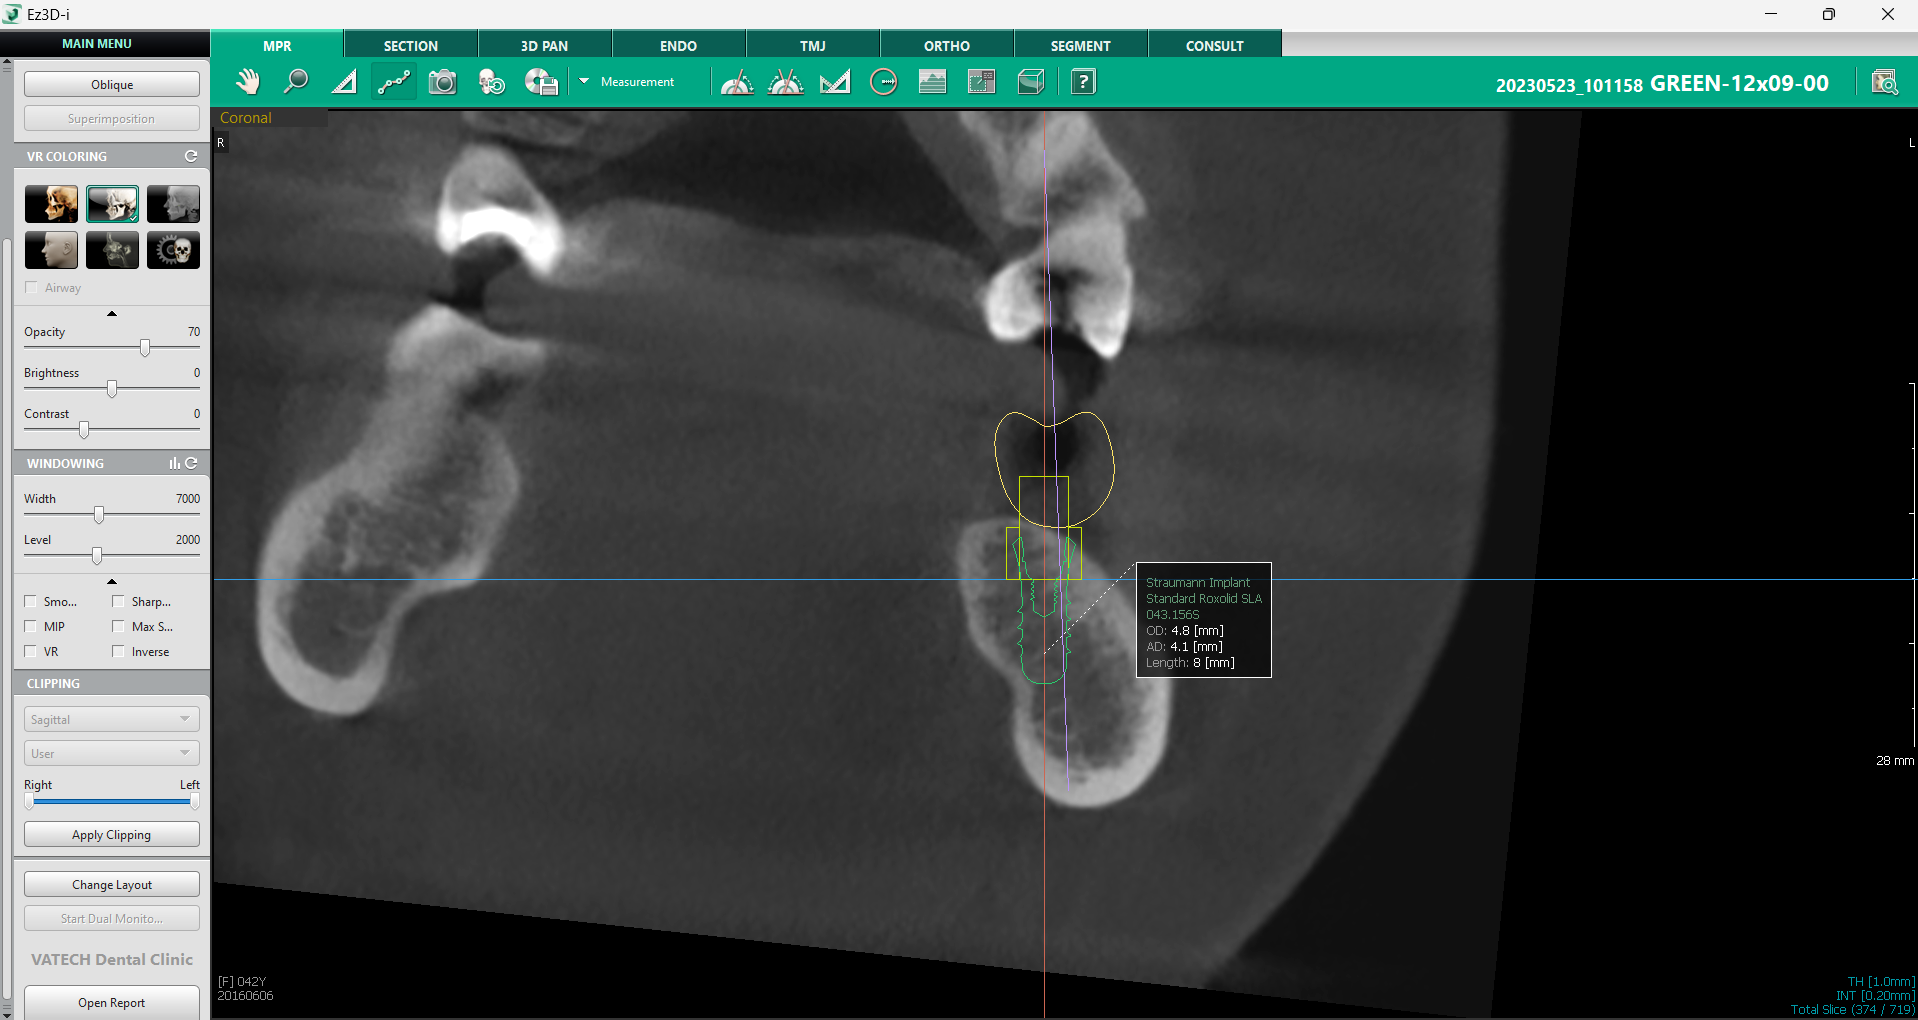

c. Informații despre implant

Un alt aspect crucial în procesul de verificare este accesul facil la toate informațiile relevante despre implant. Vizualizarea MPR oferă opțiunea de afișare detaliată a caracteristicilor implantului, facilitând organizarea și planificarea procedurii. Printr-un simplu click dreapta pe implant și selectarea opțiunii „Show Info”, se pot accesa toate detaliile esențiale, inclusiv tipul implantului, dimensiunea, linia de produse și alte specificații tehnice.

Această funcție este deosebit de utilă pentru coordonarea echipei medicale, deoarece permite o gestionare clară a fiecărui pas din procedură. Odată ce informațiile nu mai sunt necesare, ele pot fi ascunse rapid printr-un click nou pe implant și selectarea opțiunii „Hide Info”.